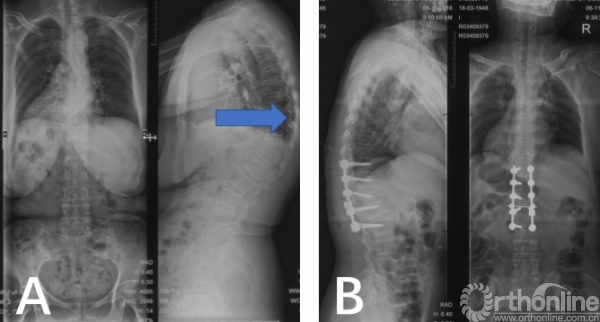

图4 病例1术前术后影像学资料

病例1,52岁女性患者,术前影像学提示脊柱后凸畸形压迫内脏。患者在我科接受侧弯纠正手术,术中采用“蛇眼一针法“进行椎弓根螺钉定位,术后显示后凸畸形纠正满意,椎弓根钉置入良好(图4)。